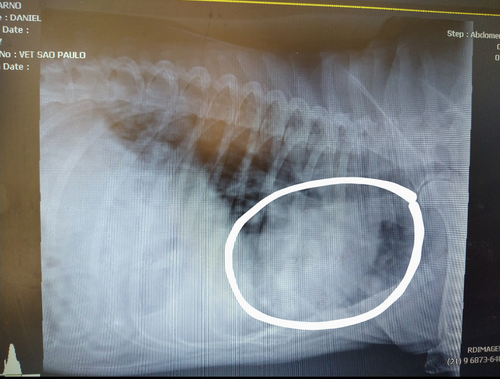

Aqui é onde mostra o tumor nos meus pulmões 😥